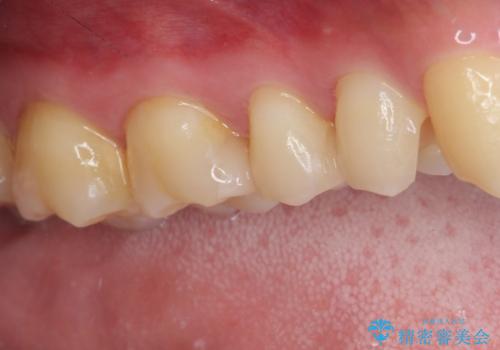

詰め物が外れた セラミックインレー修復

- 以前治療した詰め物が外れてしまい、冷たいものがしみることを主訴として来院された患者様です。

むし歯がないことを確認し、セラミックインレーにて修復するととしました。

適合の良いセラミックインレーの装着により、冷たいものがしみる症状はなくなりました。